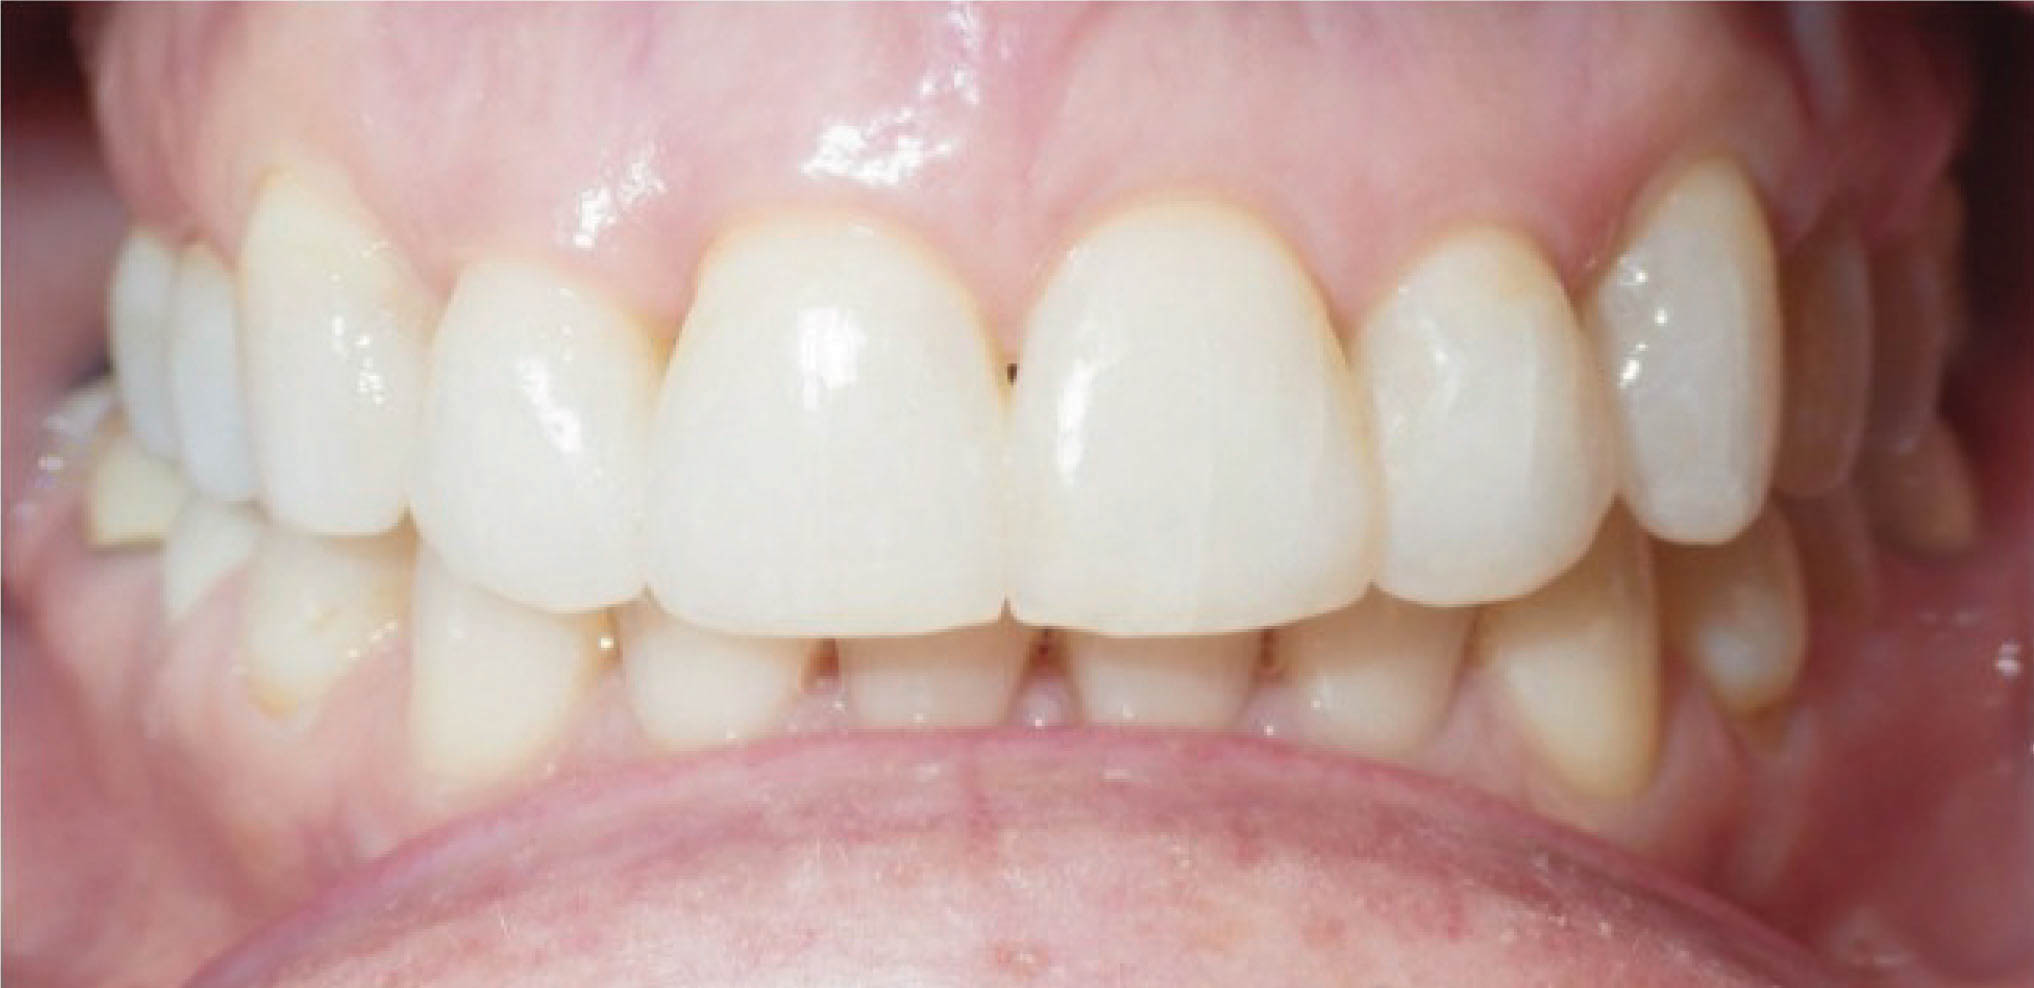

: حذف مثلث تاریک بین دندانی

با استریپ میتوان مثلث تاریک بین دندانی را از بین برد. این حالت در بیمارانی که تحلیل لثه دارند یا فرم تاج مثلثی است دیده میشود. این بیمار (شکل 152-6) از مثلث تاریکی که بین سانترالهای بالا بود ناراضی بود.

شکل152-6

در طرح درمان کامپیوتری (شکل 153-6) استریپ بالا انجام گرفت تا با عقب کشیدن انسیزورها به ظاهر زیباتری برسیم. نتیجه درمان در شکل 154-6 مشخص است.

شکل153-6

شکل154-6